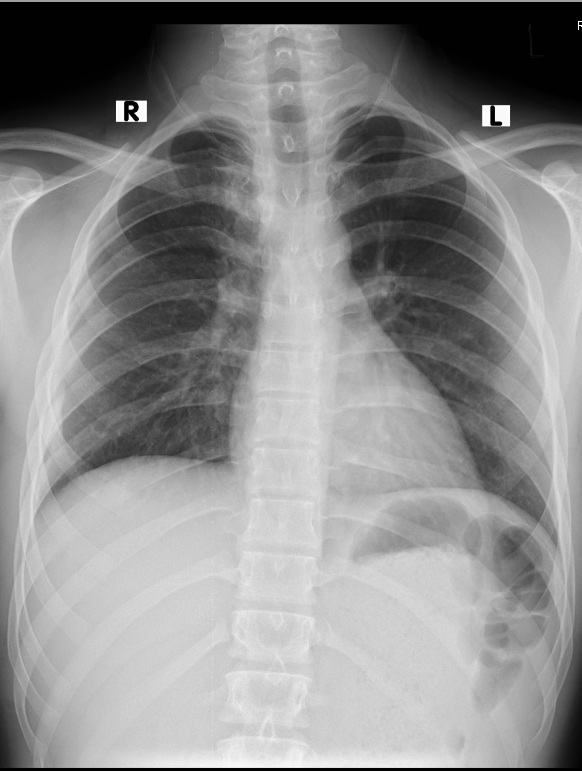

The patient was diagnosed as having a bronchogenic cyst. The authors decided to treat the patient surgically. The patient underwent a right-sided posterolateral thoracotomy via the fifth intercostal space. A round, smooth, uniform, soft, cystic mass in the posterior mediastinum was found, measuring 3.5 x 2 x 3 cm. The mass was extrapleural, adherent to the esophagus and trachea posteromedially, to the apical lobe of the lung anterolaterally, and to the azygous vein inferiorly. The pleural layer was peeled off the mass. The mass was dissected free from surrounding structures and was found to be growing from the right main bronchus from a pedicle. The pedicle was found to be cartilaginous on palpation. The pedicle was ligated, and the mass was excised. The pleura was closed back with Vicryl sutures. The chest cavity was washed with normal saline and checked for air leak. Two chest tubes were placed: posteroapically and posterobasally. Routine chest closure was performed. The patient was extubated and subsequently shifted to the ward in stable condition. Postoperatively, chest x-ray showed a fully expanded lung with no residual opacity. On the second postoperative day, the chest tubes were removed and the patient was discharged.